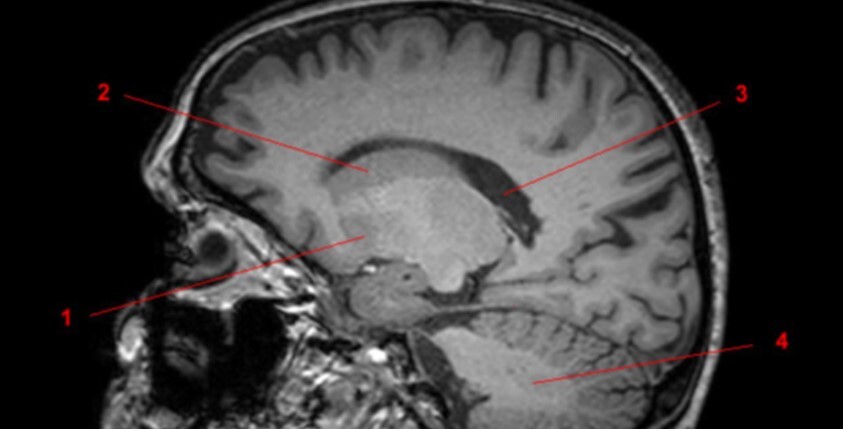

Label 1-3

Label 1-4

Label 1-5

Label 1,3,4,5,7

1=3rd ventricle

3-Anterior commissure

4=Pineal gland

5=Choroid plexus

7=Posterior commissure

Label 4,5,6,8,9

4=Genu, CC

5=Lt lateral ventricle (body)

6=Head of Rt caudate nucleus

8-Rt Lentiform nucleus

9=Lt lateral ventricle (post. horn)

Label 2,18,19,21

2=Rt internal capsule

18=Frontal sinus

19=Septum pellucidum

21=Lt external capsule